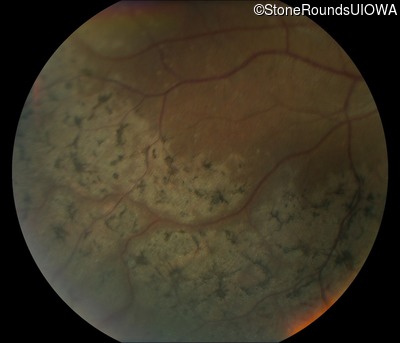

Fundus Photography - Right - 20/32 -1

Exemplar